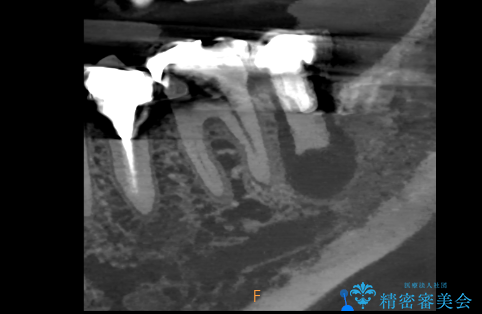

- 過去にヘミセクションが行われていたと思われる左下7番は、大きな歯根嚢胞および根尖病変が認められ、さらに骨縁下カリエスを伴っており、歯肉には瘻孔が形成されている状態でした。

保存は困難と判断し、左下7番は抜歯即時インプラントによる治療を行いました。